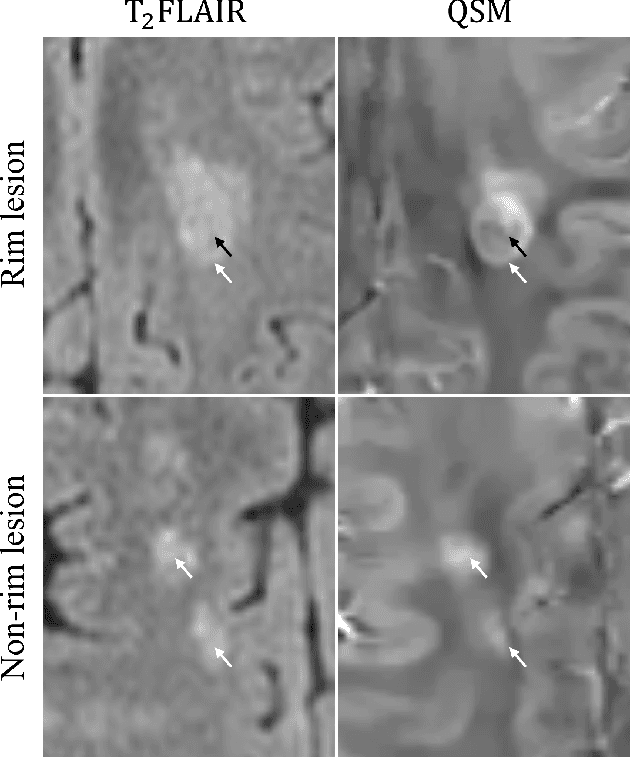

Abstract:Quantitative susceptibility maps from magnetic resonance images can provide both prognostic and diagnostic information in multiple sclerosis, a neurodegenerative disease characterized by the formation of lesions in white matter brain tissue. In particular, susceptibility maps provide adequate contrast to distinguish between "rim" lesions, surrounded by deposited paramagnetic iron, and "non-rim" lesion types. These paramagnetic rim lesions (PRLs) are an emerging biomarker in multiple sclerosis. Much effort has been devoted to both detection and segmentation of such lesions to monitor longitudinal change. As paramagnetic rim lesions are rare, addressing this problem requires confronting the class imbalance between rim and non-rim lesions. We produce synthetic quantitative susceptibility maps of paramagnetic rim lesions and show that inclusion of such synthetic data improves classifier performance and provide a multi-channel extension to generate accompanying contrasts and probabilistic segmentation maps. We exploit the projection capability of our trained generative network to demonstrate a novel denoising approach that allows us to train on ambiguous rim cases and substantially increase the minority class. We show that both synthetic lesion synthesis and our proposed rim lesion label denoising method best approximate the unseen rim lesion distribution and improve detection in a clinically interpretable manner. We release our code and generated data at https://github.com/agr78/PRLx-GAN upon publication.